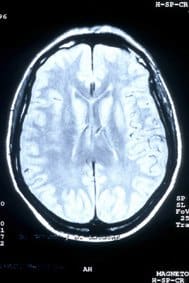

Il cervello ed il sistema nervoso sono ormai completamente formati e funzionanti. Il cervello è sufficientemente maturo per assicurare le funzioni vitali del bambino quando non dipenderà più dalla madre: respirare, avere una circolazione autonoma, mettere in moto l’apparato digestivo. ...

La migrazione delle cellule nervose è terminata e sono definitivamente acquisite. Ogni cellula è al suo posto, nelle diverse parti del cervello che termina la sua formazione all’inizio del sesto mese. ...